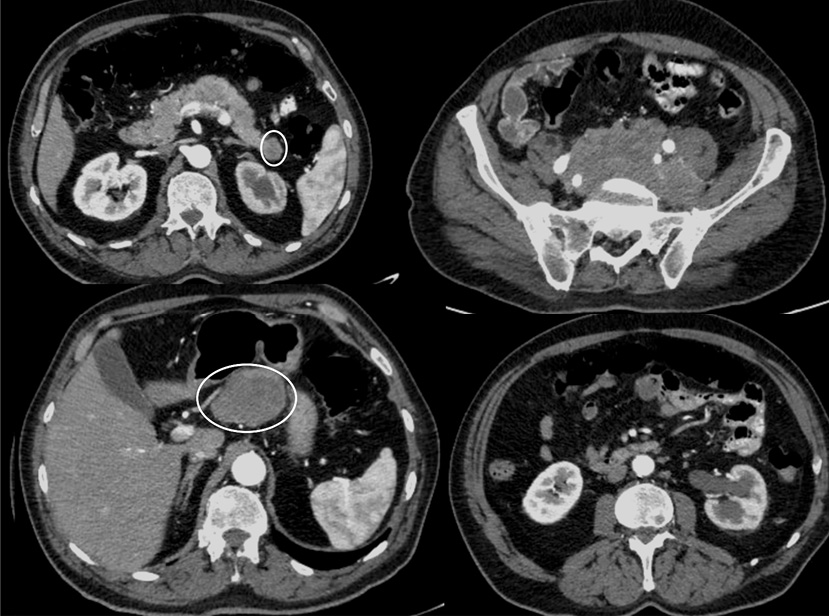

После 2 мес терапии абиратероном отмечалось прогрессирование в виде увеличения размера и количества метастатических очагов в печени, размеров абдоминальных и тазовых лимфатических узлов, появление метастатических очагов в поджелудочной железе, правом надпочечнике, парагастральных лимфатических узлах и развитие гидронефроза 2-й степени слева (рис. 6, 7).

Рис. 7. КТ органов брюшной полости после 2 мес лечения. Отмечается появление опухолевого очага в хвосте поджелудочной железы (левый верхний слайд), поражение парагастральных лимфоузлов (левый нижний слайд), увеличение размеров конгломерата подвздошных лимфоузлов со сдавлением левого мочеточника (правый верхний слайд), формирование гидронефроза слева с расширением чашечно-лоханочной системы (правый нижний слайд).